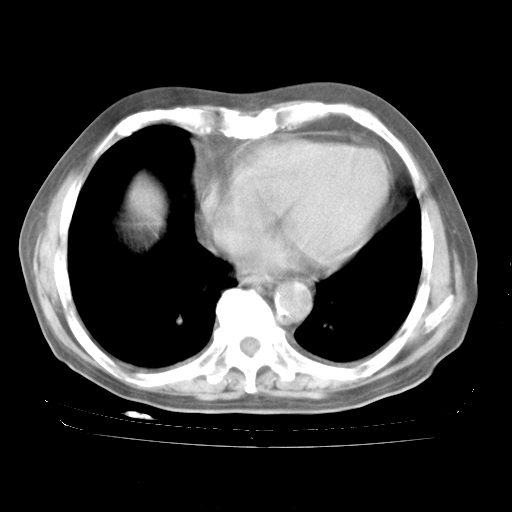

4月28日肺部CT